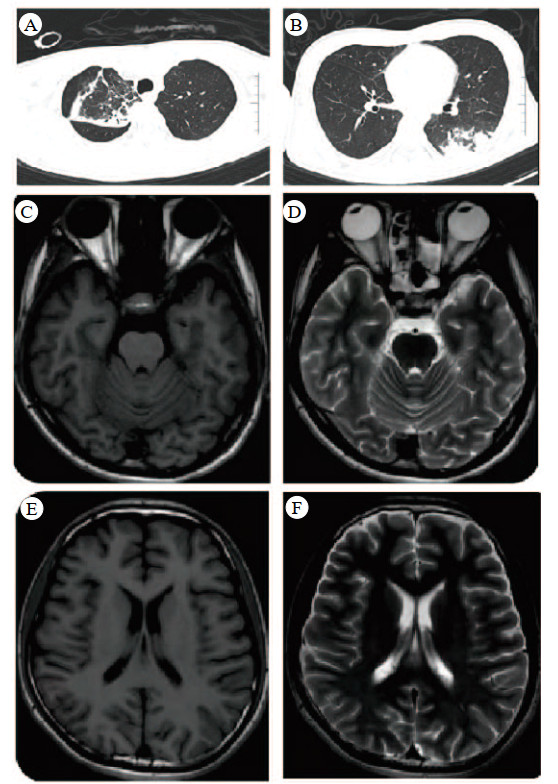

入院查体:体温36.9 ℃,心率135次/min,呼吸12次/min,血压95/56 mmHg(1 mmHg=0.133 kPa)。发育正常,营养中等。神志昏迷,癫痫持续状态,经口气管插管接呼吸机辅助通气。全身皮肤、巩膜无出血点、瘀斑及黄染。双瞳孔等大等圆,直径1 mm,对光反射迟钝。双肺呼吸音粗,可闻及少量湿啰音。心率135次/min,律齐,未闻及病理性杂音。腹部平坦,未见胃肠型及蠕动波,腹软,肝脾肋下未扪及,肠鸣音正常。四肢肌力、肌张力不合作,病理征未引出。辅助检查:血常规示白细胞12.6×109/L,血红蛋白146 g/L,血小板223×109/L;肝肾功能正常。心肌酶学:肌红蛋白258.0 μg/L,肌酸激酶684.0 U/L,肌酸激酶同工酶32.0 U/L。血清胆碱酯酶8 649 U/L。凝血功能:D-二聚体0.13 mg/L,纤维蛋白原167 mg/dL,APTT 31.3 s,TT 18.7 s。C反应蛋白50.95 mg/L。血气分析:pH 7.40,PaCO2 34.7 mmHg,PaO2 66 mmHg,SaO2 100%,吸氧浓度40%,乳酸3.1 mmol/L。心电图示窦性心动过速。影像学检查:头颅CT未见明显异常;胸部CT提示右肺上叶部分毁损,右肺上叶及左肺下叶多发感染灶,双肺多发肺泡出血(图 1 A~B)。头颅MRI未见异常信号或强化灶(图 1 C~F)。

| 图 1 肺部CT(A、B)和头部MRI(C-F) |